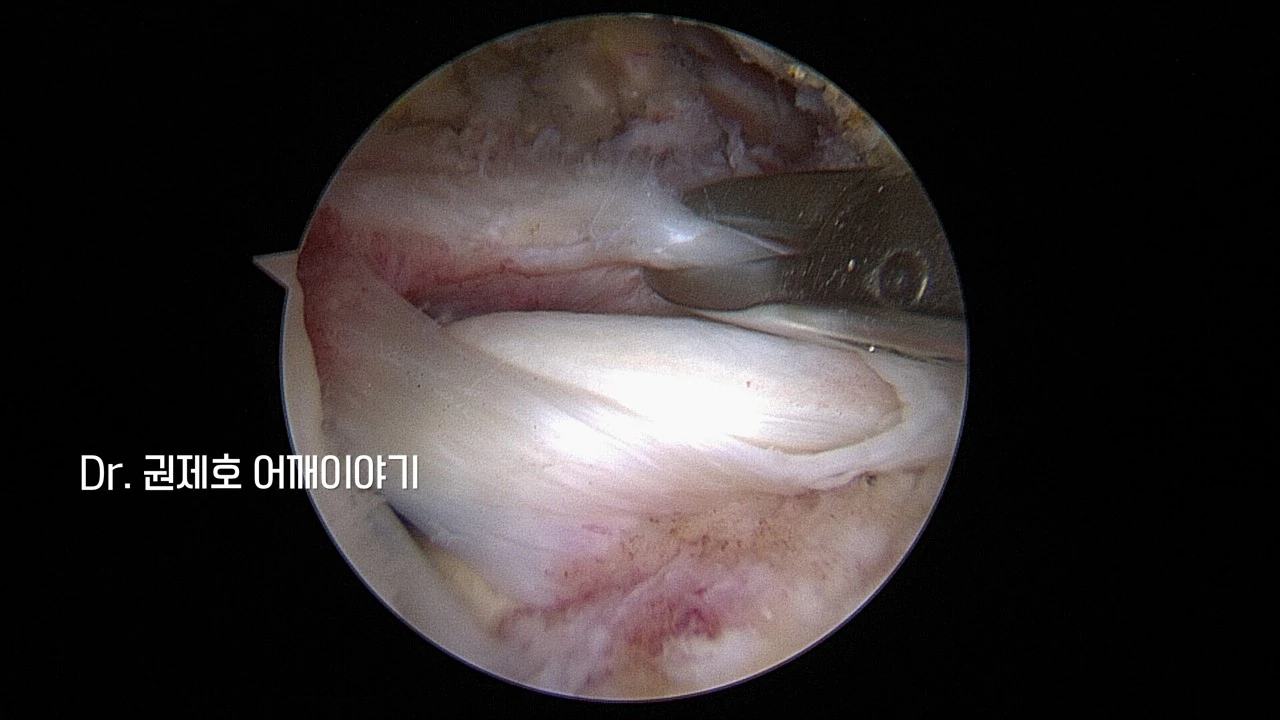

처음에는 관절에서 관찰하게 된다. 관절의 천정이 회전근개이기 때문에 관절 속에서 하늘 쪽으로 바라보면 구멍 난 회전근개가 보인다. 완전 파열을 뜻한다.

이제 회전근개 위에서 바라보게 된다. 위에서 아래 방향으로 쳐다보면 인대가 말리고, 헤져버린 어깨 회전근개의 상태를 알 수 있다. 저 사진은 집게를 이용해서 파열된 인대가 유동적인지 보고 있는 모습이다.